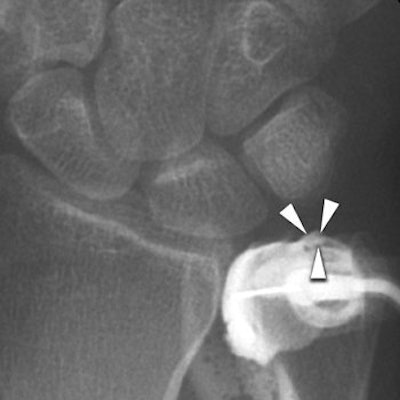

![]() |

| Same patient as above. Conventional arthrogram of distal radioulnar joint shows contrast agent pooling in triangular fibrocartilage defect (arrowheads). Rüegger C, Schmid MR, Pfirrmann CWA, Nagy L, Gilula LA, and Zanetti M. "Peripheral Tear of the Triangular Fibrocartilage: Depiction with MR Arthrography of the Distal Radioulnar Joint" (AJR 2007; 188:187-192). |